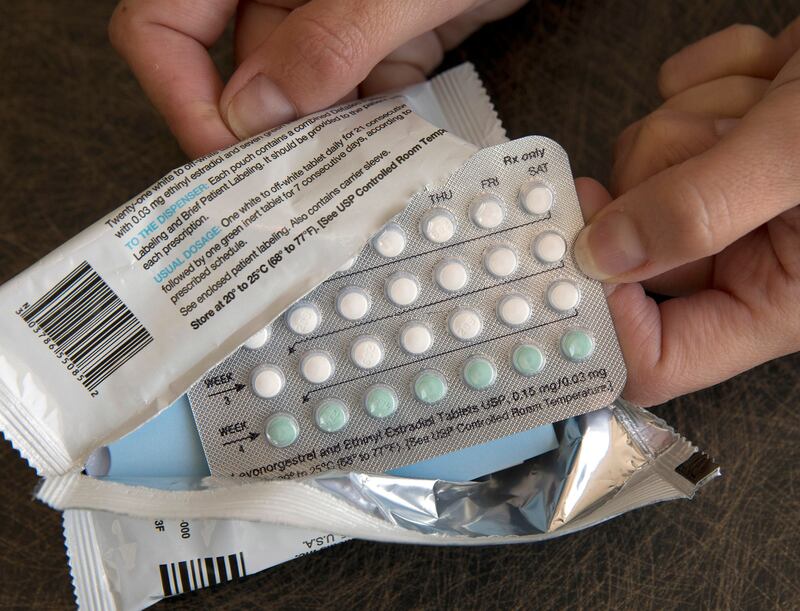

Para las mujeres con trombofilia, el uso de anticonceptivos orales aumenta hasta 30 veces el riesgo de coágulos en el torrente sanguíneo. Por ello, es importante descartar el diagnóstico en la edad adulta temprana antes de empezar a tomarlos. Si se confirma la enfermedad se recomendará optar por métodos anticonceptivos no orales.

Lo mismo ocurre durante la menopausia, cuando a las mujeres se les prescribe reemplazo hormonal. Si la presencia de la enfermedad es conocida se debe optar por no hacerlo o elegir opciones que se consideren más seguras.

Para evitar complicaciones es necesario tratar la enfermedad con el uso de anticoagulantes, especialmente durante el embarazo. También se deben tomar otras medidas preventivas para eliminar los riesgos ambientales de trombosis. Además de no usar hormonas, es necesario evitar la obesidad y el tabaquismo y tener mucho cuidado en vuelos largos: beber mucho líquido, no consumir alcohol y levantarse cada 50 minutos.

La segunda, la mutación en el gen de la Protrombina asociada con el aumento de la concentración de protrombina en plasma, aumenta el riesgo de tromboembolismo venoso y trombosis cerebral. Las personas con esta mutación genética tienen un riesgo seis veces mayor de sufrir una trombosis venosa. El riesgo aumenta considerablemente en el embarazo por el uso de anticonceptivos orales.

Si la paciente es portadora heterocigota de ambos genes (Factor V y Protrombina), el riesgo de sufrir un ACV puede aumentar hasta 149 veces si ella utiliza anticonceptivos orales. Por lo tanto, la prueba de ADN para detectar la mutación de estos dos genes es importante para cualquier mujer que pretenda usar este método anticonceptivo, quedar embarazada o iniciar una terapia de reemplazo hormonal, especialmente para aquellas con antecedentes familiares de trombosis.